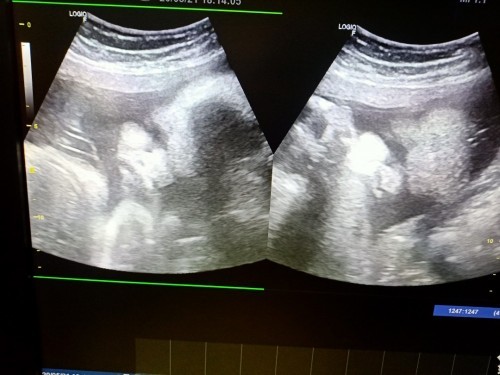

ตอนนี้แม่ได้ 33+1 แล้วหมอบอก นน.น้องอยู่ที่2 กิโล กินยังไงให้ นน.เด็กขึ้นเยอะๆค่ะ ตอนนี้ นน.ไปลงที่แม่หมดเลย😅😅